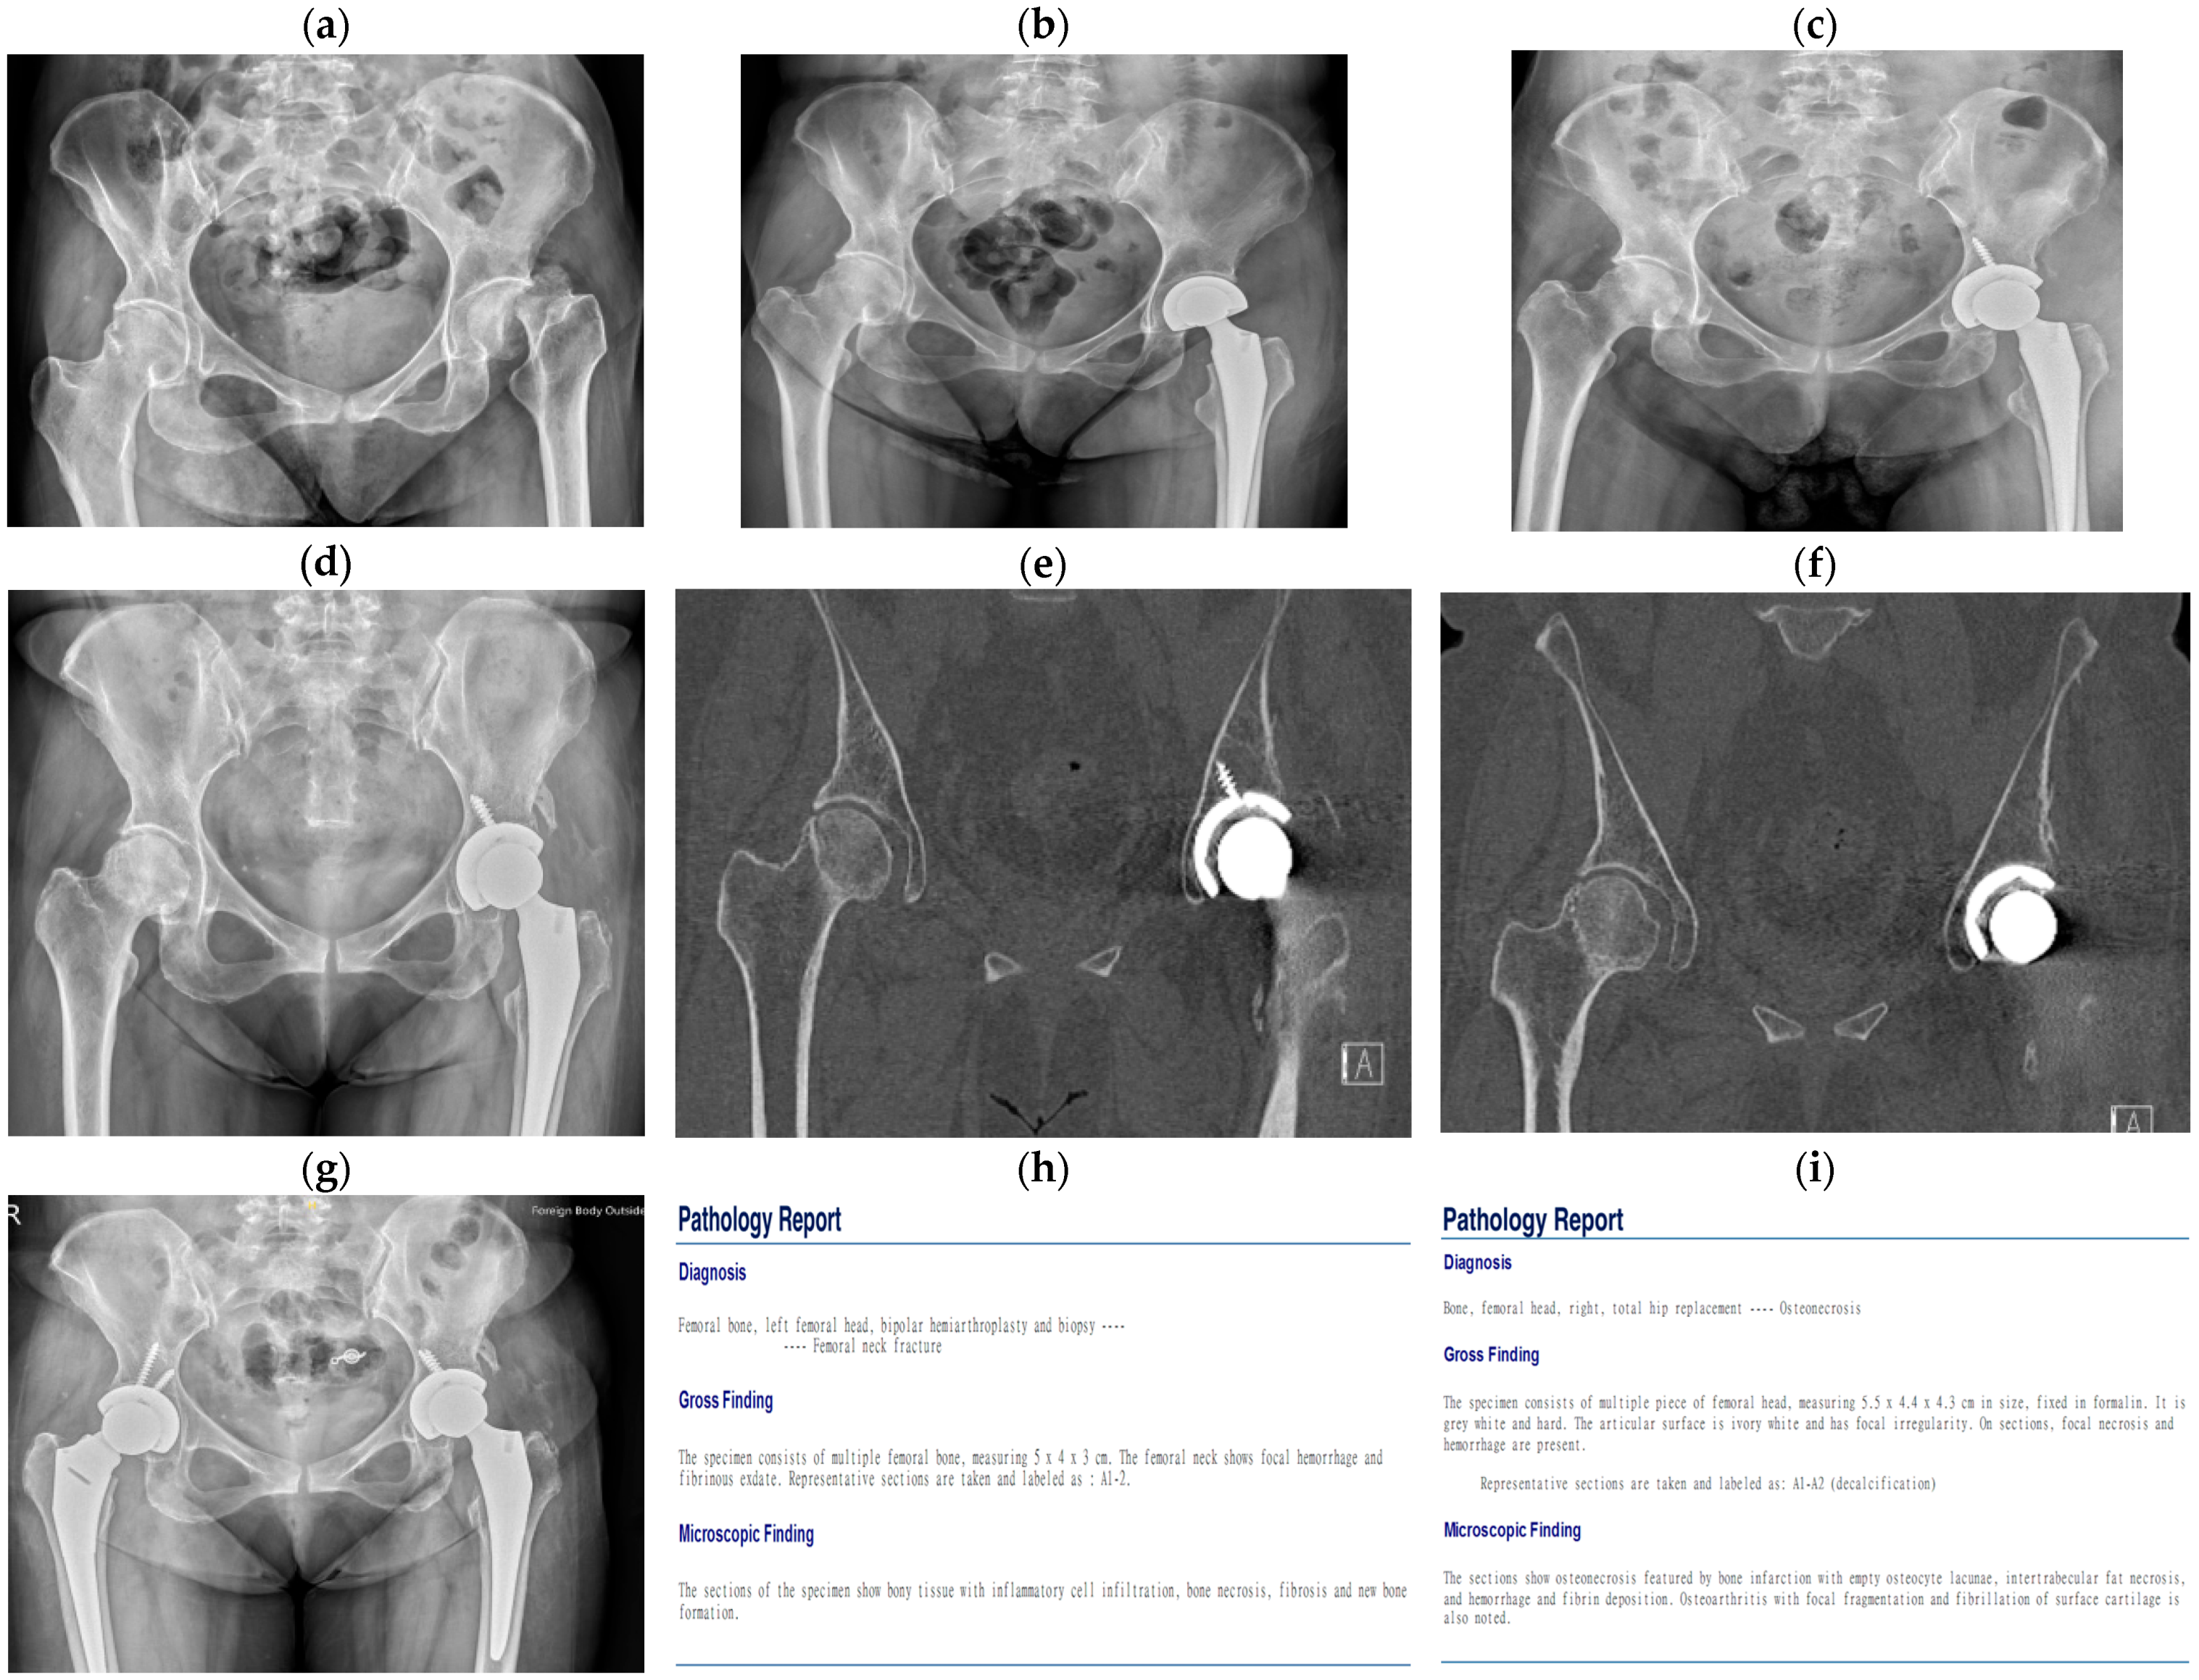

| Case | Age | Gender | Underlying | Risk Factors | Fracture Site | Trauma History | Diagnostic Tool | Surgical Treatment |

| No. 1 | 55 | Male | Hypertension | Alcoholic | Subcapital | No | X-ray | 1. Cannulated screws 2. THA |

| No. 2 | 52 | Female | Liver cirrhosis | Alcoholic | Subcapital | No | X-ray CT | 1. Bipolar 2. THA |